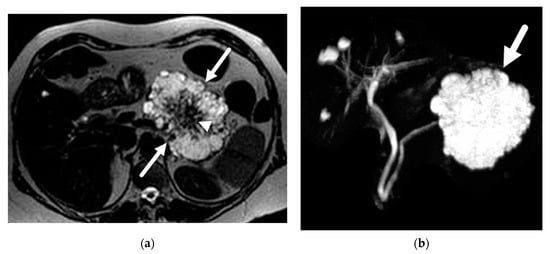

- Mamone, G.; Barresi, L.; Tropea, A.; Di Piazza, A.; Miraglia, R. MRI of mucinous pancreatic cystic lesions: A new updated morphological approach for the differential diagnosis. Updates Surg. 2020, 72, 617–637. [Google Scholar] [CrossRef] [PubMed]

- Giambelluca, D.; Bruno, A.; Picone, D.; Midiri, M. The honeycomb pattern of pancreatic serous cystadenoma. Abdom. Radiol. 2019, 44, 1191–1192. [Google Scholar] [CrossRef]